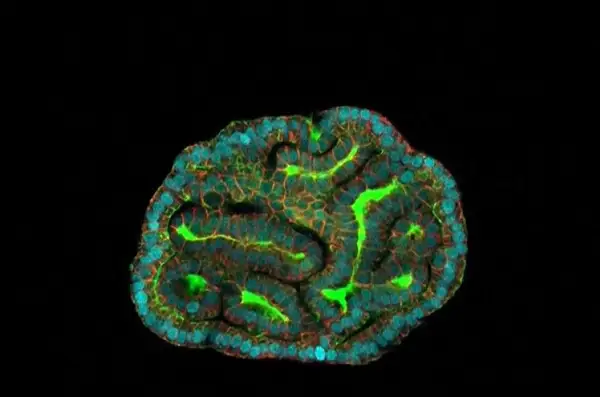

Britským vedcom sa podaril vzácny objav. Z častíc, ktoré sú v plodovej vode, vytvorili miniorgány, takzvané organoidy. Ich pomocou dokážu odhaliť skrytú chorobu plodu dieťaťa počas tehotenstva.

Vedci univerzity College London získavajú bunky, ktoré do plodovej vody vylučujú počas vývinu obličky, pľúca a črevá dieťaťa. V Petriho miske ich kultivujú na mini orgány.

„Tieto organoidy majú obmedzenú životnosť, preto musíme byť rýchli. Obsahujú však kompletnú informáciu o funkcii epitelu, teda vnútornej vrstvy orgánu. V praxi to znamená, že funkciu orgánu dokážeme napodobniť v Petriho miske a zistiť prípadné defekty plodu dieťaťa, priblížil detský chirurg Paolo de Coppi.